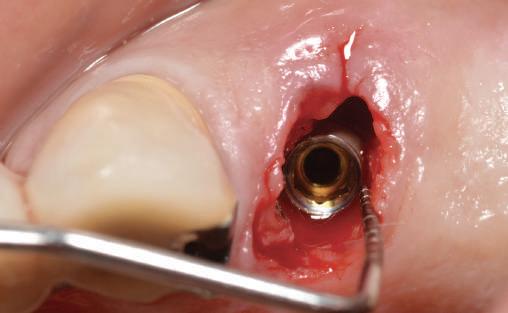

Conform informațiilor oferite de CBCT, pe pozițiile molarilor 36 și 37 au fost inserate două implanturi Ankylos (Dentsply Implants) C/X A 11 (diametru 3.5 mm, lungime 11 mm).

Datorită stabilității primare la inserare de aproximativ 35 Ncm pentru ambele implanturi, am optat pentru înșurubarea bonturilor intermediare conice Balance Base Narrow Straight GH 3.0 și vindecare transgingivală (fig. 2, 3). Inserarea acestor stâlpi s-a realizat la un cuplu de forțe de 25Ncm, cu ajutorul unei chei dinamometrice, aplicându-se ulterior cape de protecție (fig. 4). Vindecarea transgingivală postoperatorie a decurs fără complicații.

Figurile 1. Status clinic şi radiologic iniţial; 2. Bontul Balance Base Narrow Straight GH 3.0; 3. Bonturile Balance Base Narrow aplicate imediat post-inserare la 25 Ncm; 4. Aplicarea capelor de protecţie şi sutura; 5. Stâlpii de amprentă înşurubaţi la nivelul bonturilor Balance Base Narrow;